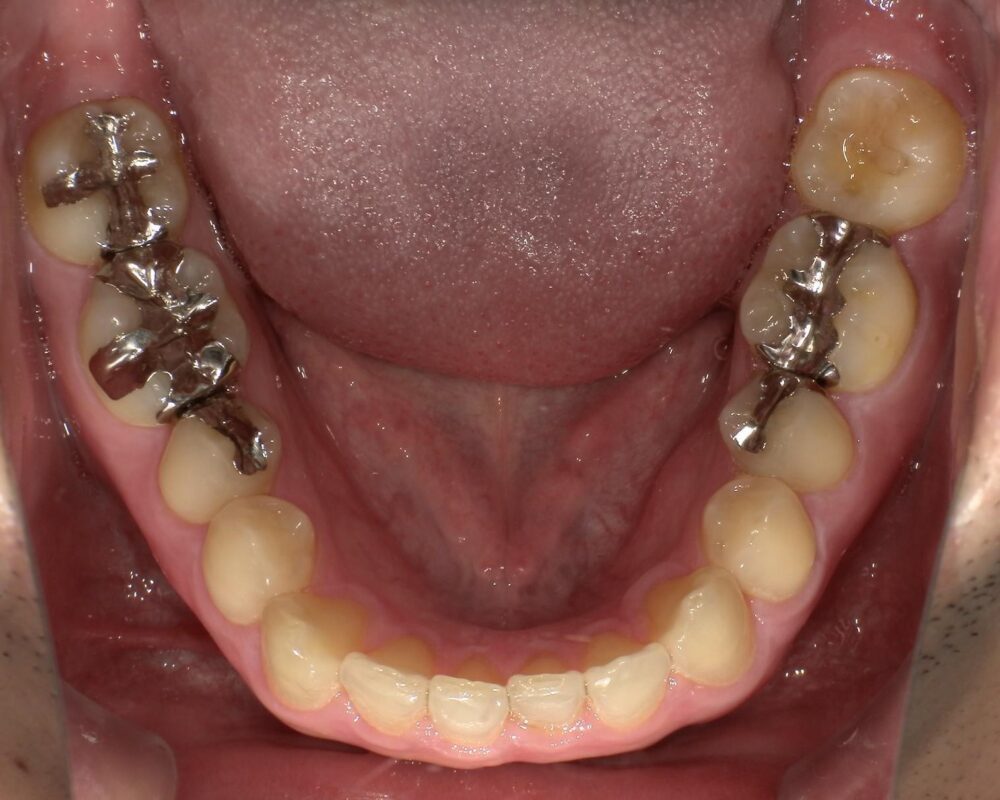

症例3

治療前

| 主訴 | 虫歯を治したい |

|---|---|

| 診断 |

2次虫歯 |

| 治療内容 | 保険CAD インレーによる修復治療 |

| 年齢・性別 |

29歳男性 |

| 治療期間 |

2ヶ月 |

| 治療費用 | 保険に準ずる。 |

| リスク・副作用 | CADの破折、着色 |